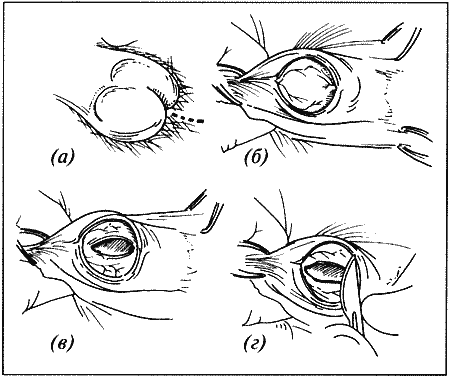

Вагинальная эндоскопия

Прекращение секреции эстрадиола фолликулами и переход их к секреции прогестерона приводят к снижению как отечности, так и васкуляризации слизистых оболочек, что сопровождается выраженным изменением характера вагинальных выделений, выявляемым с помощью вагинальной эндоскопии. На стадии проэструса слизистая оболочка становится более выпуклой и отечной, затем наблюдается ее уменьшение; по мере приближения овуляторного пика слизистая сжимается и бледнеет, в некоторых случаях становясь практически белой (фиг. 1.1). Перечисленные изменения свидетельствуют о приближении стадии, характеризующейся постепенным повышением концентрации прогестерона перед овуляцией и последующим наступлением фертильного периода. Эти изменения легко узнать, имея даже небольшую практику (фиг. 1.3), кроме того, они настолько воспроизводимы, что по набору признаков их можно оценивать полуколичественно. Вагинальная эндоскопия весьма полезна в определении оптимальных сроков вязки. По окончании фертильного периода, т. е. в начале метэструса — слизистая оболочка влагалища бледнеет и истончается, складки становятся закругленными — и что, вероятно, является наиболее характерным признаком, — слизистая в переднем отделе влагалища выглядит раздраженной и при прикосновении быстро сжимается, образуя розетку.

Фиг. 1.3.

Эндоскопическое исследование слизистой влагалища. Динамика изменений на протяжении цикла: (а) проэтрус — розовая окраска и отечность; (b) начало эструса — слизистая бледнеет, отек начинает уменьшаться (обычно перед пиком ЛГ); (c) середина эструса — слизистая бледная, уменьшение отека (сморщивание) явно выражено, что соответствует середине фертильного периода; (d) начало метэструса — видны закругленные складки, при прикосновении слизистая смыкается, образуя розетку (е) (см. Приложение)